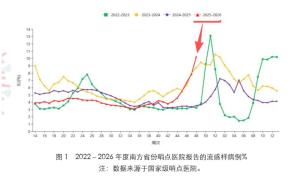

今年流感为啥这么“凶” 流行毒株变化助长威力

2025-12-07 17:36

今年流感为啥这么凶